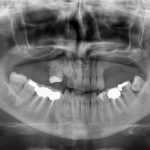

In questo articolo viene presentato un metodo che ha previsto l’utilizzo della tecnologia digitale per eseguire una riabilitazione full-arch in tempi differiti. La raccolta dei dati in formato digitale e le immagini di radiologia 3D hanno consentito di sviluppare un’unica, completa pianificazione delle procedure per affrontare un caso complesso attraverso più interventi chirurgici e protesici in momenti diversi;

Nella riabilitazione implanto-protesica può rendersi necessario l’inserimento di impianti angolati rispetto agli elementi dentali adiacenti. Gli autori riportano la loro esperienza nell’utilizzo di un nuovo dispositivo implantare che consente di protesizzare impianti multipli inseriti con un disparallelismo reciproco fino a 15°, senza interposizione di meso-strutture e senza ricorrere a monconi con ingaggio antirotazionale. Questo permette di utilizzare impianti più lunghi e di conservare un ingombro verticale ridotto, massimizzando l’interazione con il tessuto osseo.

Molti motivi spingono i ricercatori ad approfondire l’applicazione del laser nelle procedure di chirurgia orale e implantologia. Nello specifico, si avverte la necessità di realizzare protocolli ampiamente validati che prevedono l’uso del laser per la decontaminazioni di siti infetti finalizzata al posizionamento di impianti di tipo 1. In questo aggiornamento monografico, dopo una revisione della letteratura viene presentato uno studio clinico controllato che dimostra come il posizionamento immediato di un impianto in un sito post-estrattivo infetto o infiammato, dopo la decontaminazione laser, non sembra aumentare il rischio di fallimento

Le strutture anatomiche dell’osso mascellare presentano molti aspetti di rilevanza clinica che devono essere valutati nella formulazione e nella esecuzione di un piano di trattamento implantare. La presentazione di alcuni casi clinici evidenzia le criticità presenti nella zona frontale e il modo per riparare a possibili errori procedurali.